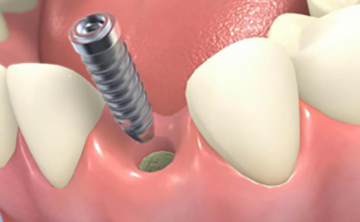

インプラントとは、虫歯や歯周病などの様々な原因により歯が失われてしまったところへ、人工の歯の根=人工歯根(インプラント)をつくり、その上に被せ物を装着する治療法のことです。

インプラントの構造は、上部構造・アバットメント部(支台部)・歯根部の3つの構造から成り立っています。

上部構造は、いわゆる被せものを指しており、歯の部分です。

アバットメント(支台部)は、上部構造と歯根部をつなぐ役割を果たしています。

歯根部は、チタン製で、この部分と顎の骨が結合します。